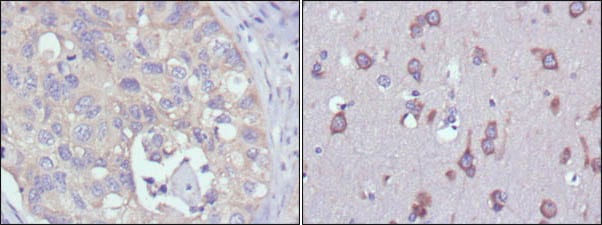

分类: 科研抗体货号: 20354别名: KIA; Ki-67; MKI67应用: IHC,IF反应种属: Human,Mouse,Rat,Rabbit,Monkey